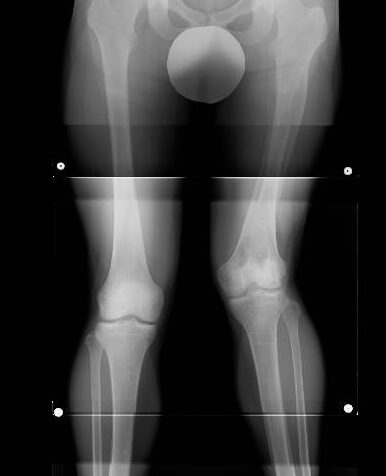

✔︎ 幼少期の交通事故の後遺症で骨端線がやられ片方の足が育たなくなり短くそして変形した(エックス脚)。脚長差も約7センチ!